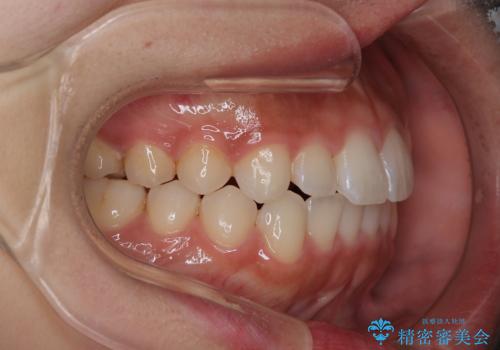

【インビザライン】がたつきをマウスピースできれいにしたい

- 20代女性

- 前歯の叢生を主訴に来院されました。非抜歯でインビザラインで治療をしました。

叢生はIPRをし、並べました。この患者様はオープンバイトだったため歯を並べる過程でかみ合わせも治しました。